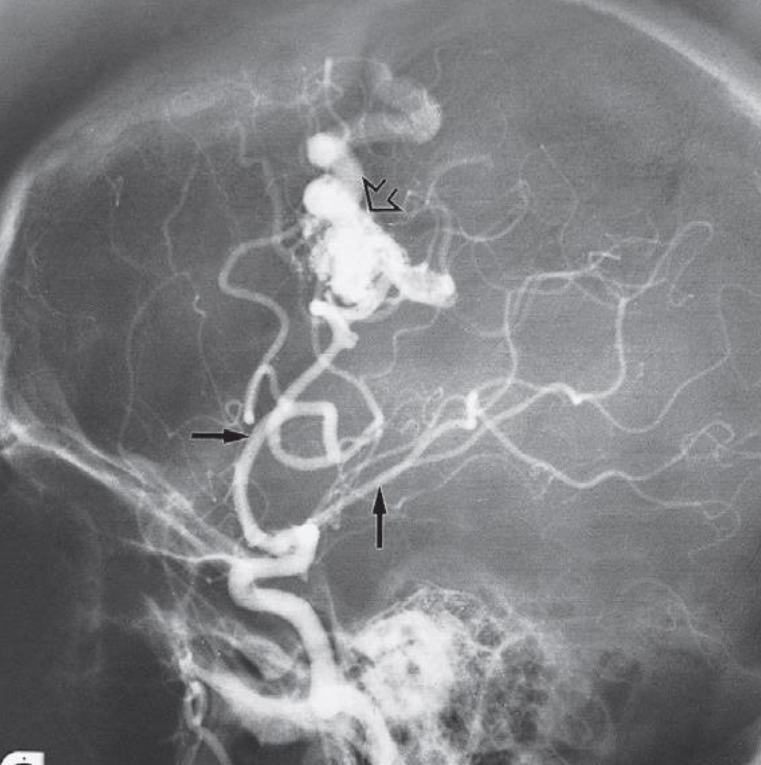

A. Imaging modality or technique or study? Digital Subtraction Angiography

B. Type or name of contrast? Iodine base